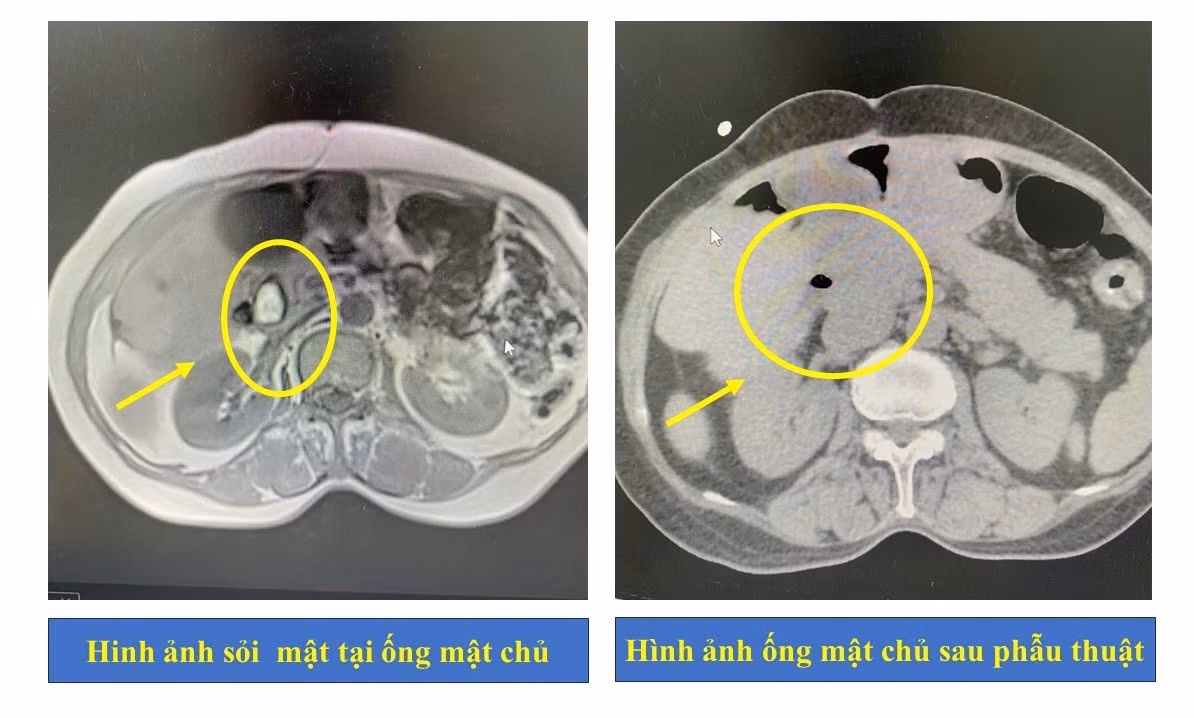

Sau khi thực hiện các cận lâm sàng cần thiết, kết quả cho thấy người bệnh bị nhiễm trùng đường mật, tắc mật do sỏi tại ống mật chủ.

Hình ảnh ống mật chủ của người bệnh trước và sau phẫu thuật - Ảnh BVCC

Người bệnh được chuyển đến Khoa Ngoại Tiêu hóa - Gan mật và chỉ định dẫn lưu đường mật qua da. Sau 5 ngày điều trị tích cực, tình trạng tắc mật và nhiễm trùng đã được cải thiện, người bệnh tiếp tục được chỉ định phẫu thuật tán sỏi đường mật qua da bằng laser – phương pháp đang được ứng dụng rộng rãi tại Bệnh viện Đa khoa tỉnh Phú Thọ.